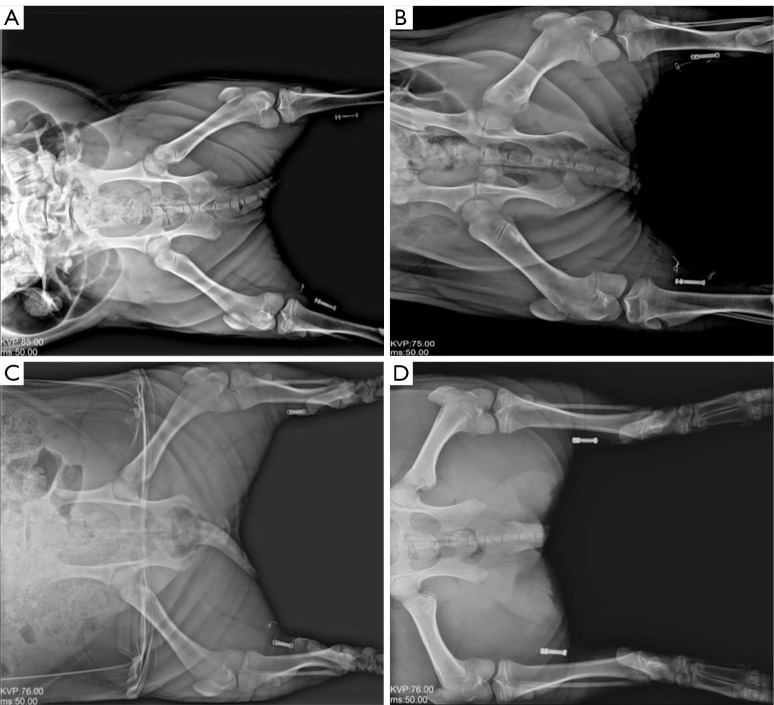

Methods: Three male Bama miniature pigs (25-28 kg) received bilateral implantation of a novel battery-free, wireless implantable TNS system. The right-side device was activated as the treatment side, and the left-side device remained inactive as a control. Postoperative observations continued for 30 days, including assessments of general health, body weight, and X-ray monitoring of device position. OAB was induced by intravesical infusion of 5% acetic acid. Bladder pressure-volume curves were measured under baseline, OAB-induced (control), and TNS-stimulated (experimental) conditions. Histological examination of tissues surrounding the implants was conducted using hematoxylin and eosin staining to assess inflammation.

Results: All pigs remained in good health throughout the study, with stable weight gain and no adverse events. The implanted devices showed no migration and maintained stable function. Compared with baseline, bladder capacity was significantly reduced in the control group after OAB induction (P<0.05), and significantly increased in the experimental group after stimulation (average improvement of 24.4%, P<0.05). Histological analysis revealed no significant inflammatory reactions at electrode contact sites or in surrounding tissues between the experimental and control groups (P>0.05).